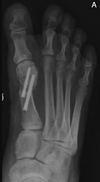

15

• Na avaliação radiográfica em AP com carga, quais os principais ângulos a serem traçados?

A

• Ângulo de valgismo do hálux (metatarsofalângico)

• Ângulo intermetatarsal

• Ângulo de valgismo interfalângico do hálux

• Ângulo articular metatarsal distal (AAMD)

How well did you know this?

16

• Na radiografia em AP com carga, como é traçado o ângulo intermetatarsal?

• Ângulo entre o eixo longo do 1° e do 2° raio

• Normal → até 9°

• Leve → 9° a 12°

• Moderado → 13° a 15°

• Grave → > 16°

17

• Na radiografia em AP com carga, como é traçado o ângulo de valgismo do hálux (metatarsofalângico)?

• Ângulo entre o eixo longo do 1° mtt e o eixo longo da falange proximal

• Normal → até 15°

• Leve → < 25°

• Moderado → 25° a 40°

• Grave → > 40°

18

• Na radiografia em AP com carga, como é traçado o ângulo de valgismo interfalângico do hálux?

• Ângulo entre o eixo longo da falange proximal e o eixo longo da falange distal

• Normal → até 10°

19

• Na radiografia em AP com carga, como é traçado o ângulo articular metatarsal distal (AAMD)?

• Traça-se uma linha unindo os dois pontos mais largos da superfície articular do 1° mtt e outra linha perpendicular a esta

• Depois, traça-se uma linha no eixo longo do 1° mtt

• O ângulo entre as duas maiores retas → até 15°